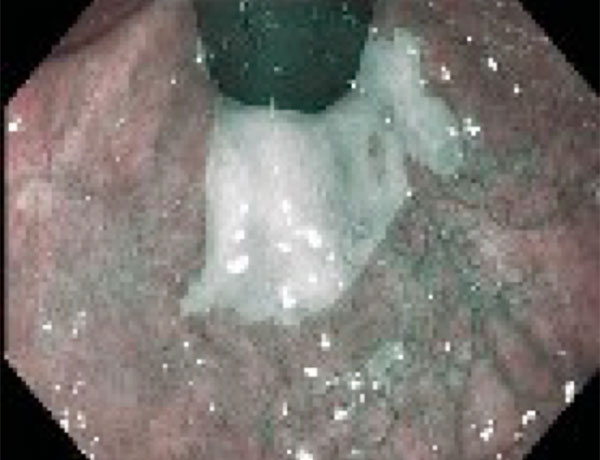

Reflünün sindirim sisteminde yarattığı hasarı görmenin en kesin yolu endoskopidir. Yemek borusuna kaçan asit hasar yarattıysa bunu görebiliriz.

Yemek Borusu Barrett Hastalığı

Uzun süreli reflü hastalarında ortaya çıkan Barrett Hastalığını, ancak endoskopi sırasında aldığımız doku örnekleri ile ayırt edebiliriz. Mide fıtıklarını görmenin ve kanıtlamanın en doğru yolu da endoskopidir.

Barrett Hastalığı

Barrett Hastalığı Nedir? Ne Kadar Ciddi Bir Sorundur?

Barrett özofagus, yemek borusunun alt ucundaki normal skuamöz epitelyumun, uzun süreli reflü nedeniyle bağırsak tipi kolumnar epitele dönüşmesi durumudur. Bu durum, metaplazi olarak tanımlanır ve bazı hastalarda displazi ya da yemek borusu adenokarsinomu riskini artırabilir.